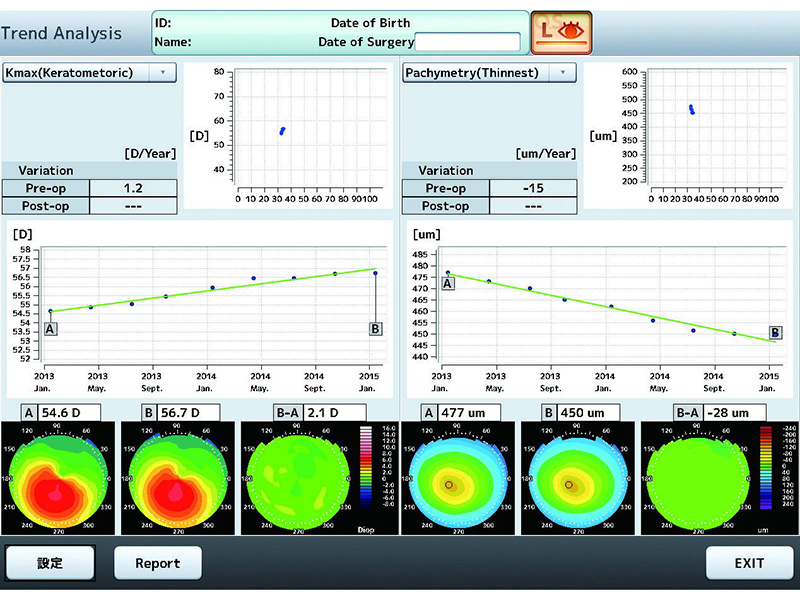

3D/2D анализ

Обзор в 3D

гониоскопия, срезы, вращения, ITC

Карты

Аксиальная сила (передняя, задняя, реальная), Сила рефракции (кератометрическая, передняя), Мгновенная сила (кератометрическая, переднаяя, задняя, реальная), Элевация (задняя, передняя), пахиметрия (карта, секторы), Эпителий, Глубина передней камеры, OCT (горизонтальная, вертикальная)

Функция анализа

Аксиальная сила (передняя, задняя, реальная), Сила рефракции (кератометрическая, передняя), Мгновенная сила (кератометрическая, переднаяя, задняя, реальная), Элевация (задняя, передняя), пахиметрия (карта, секторы), Эпителий, Глубина передней камеры, OCT (горизонтальная, вертикальная)

Экспорт видео

Просмотр в режиме 2D вращением/С-скан -3D виде